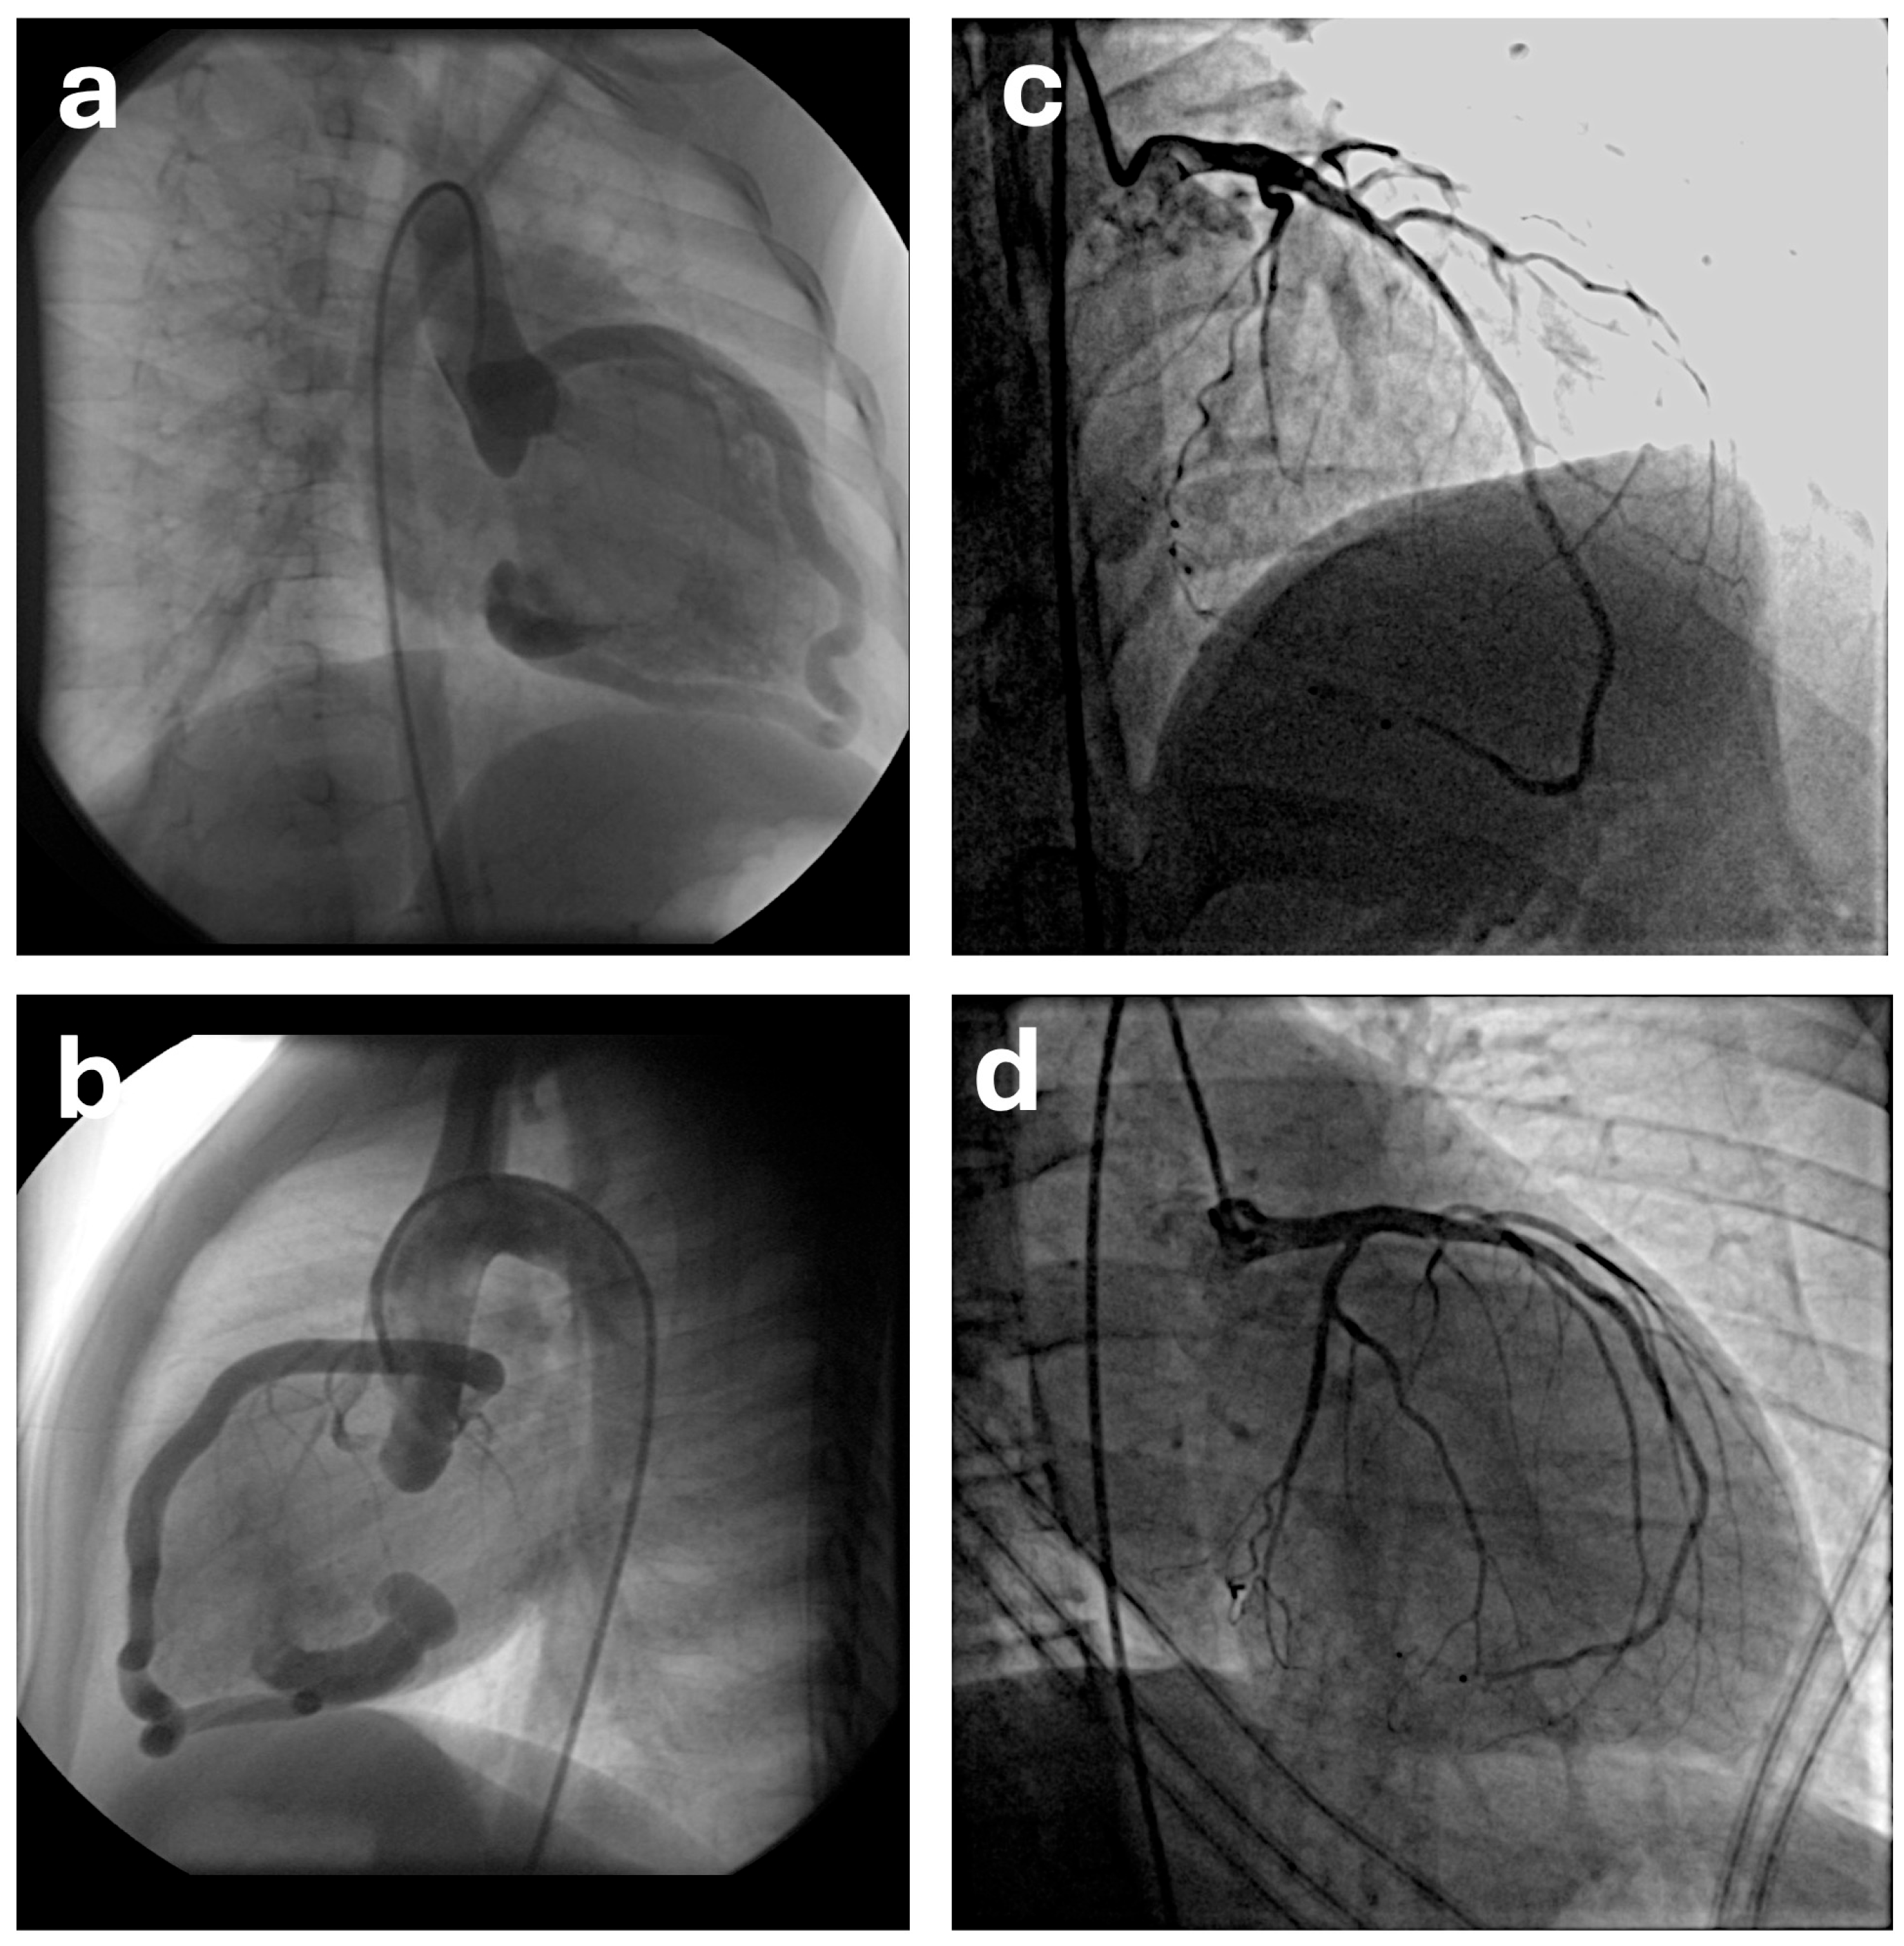

The conservative clinical follow-up approach applied in cases of asymptomatic small fistulas is also a viable option for medium and large-sized fistulas. However, medium and large fistulas frequently tend to progress [9,28]. In adults, advancing age introduces accumulating comorbidities that heighten procedural risks, and owing to the unpredictable nature of complications—even if rare—elective closure interventions are recommended [11]. Indications for coronary artery fistula closure in children generally include symptomatic cases with hemodynamically significant shunts (e.g., heart failure and myocardial ischemia), medium-to-large-sized fistulas, and patients with a history or risk of endocarditis. However, the timing of closure for medium-to-large asymptomatic fistulas during childhood remains controversial. Short-segment aneurysmal dilatations in proximal coronary artery-originating fistulas confer a high rupture risk, while coronary artery dilatations in distal fistulas predispose to slow flow-associated thrombotic complications with delayed closure; thus, childhood intervention during follow-up is generally recommended [9]. In addition, early closure facilitates more favorable remodeling (Figure 1) and potentially superior long-term outcomes, as supported by experienced centers’ data on successful transcatheter approaches even in neonates [13,14,19].

Figure 1. Angiographic demonstration of long-term coronary remodeling in Patient 15. (a,b) Pre-procedural selective coronary angiography showing a distal coronary artery fistula between the left coronary artery and the right ventricle. Transcatheter closure was performed using an Additional Size Amplatzer Duct Occluder. (c,d) Follow-up coronary angiography obtained at 155 months after the procedure demonstrating complete fistula occlusion and marked remodeling of the left coronary artery with restoration of normal distal coronary flow.